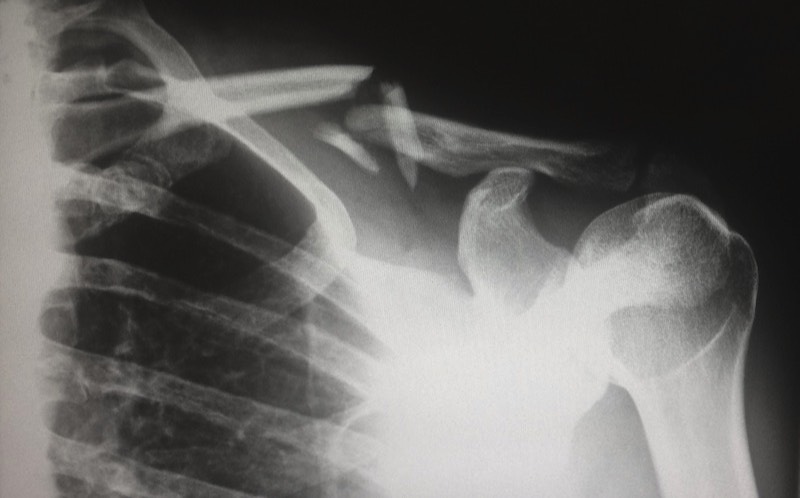

- Neck and Shoulder Pain

Moliri Consulting can assist your business by providing fully trained and accredited Osteopaths or Physiotherapists who are specialists in dealing with workplace musculoskeletal conditions.